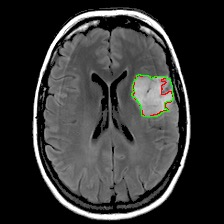

Neural processes have recently emerged as a class of powerful neural latent variable models that combine the strengths of neural networks and stochastic processes. As they can encode contextual data in the network's function space, they offer a new way to model task relatedness in multi-task learning. To study its potential, we develop multi-task neural processes, a new variant of neural processes for multi-task learning. In particular, we propose to explore transferable knowledge from related tasks in the function space to provide inductive bias for improving each individual task. To do so, we derive the function priors in a hierarchical Bayesian inference framework, which enables each task to incorporate the shared knowledge provided by related tasks into its context of the prediction function. Our multi-task neural processes methodologically expand the scope of vanilla neural processes and provide a new way of exploring task relatedness in function spaces for multi-task learning. The proposed multi-task neural processes are capable of learning multiple tasks with limited labeled data and in the presence of domain shift. We perform extensive experimental evaluations on several benchmarks for the multi-task regression and classification tasks. The results demonstrate the effectiveness of multi-task neural processes in transferring useful knowledge among tasks for multi-task learning and superior performance in multi-task classification and brain image segmentation.